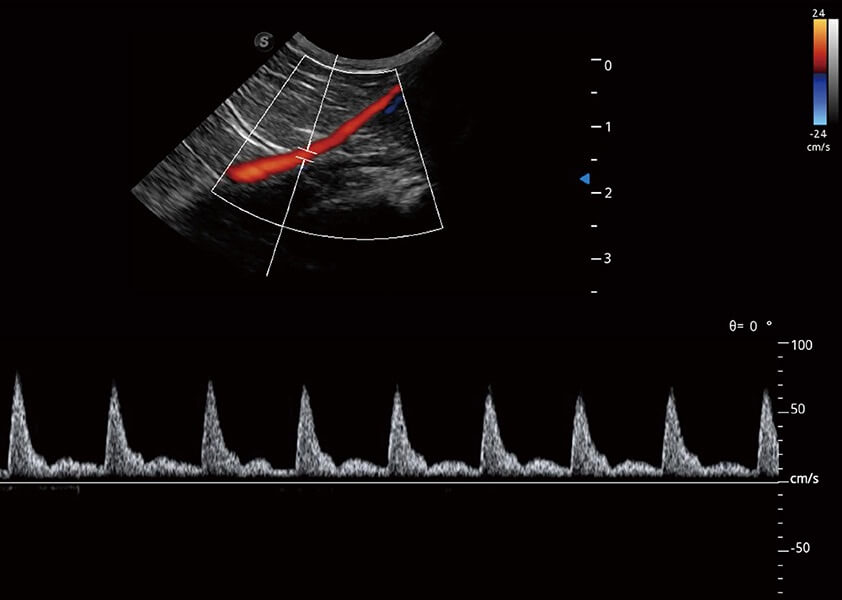

ProPet 60 作为一款高端台式动物超声设备,为动物医生的日常诊断提供了一系列贴合动物临床需求、解决临床实际问题的高级成像功能。凭借全系列高清探头,满足医生对腹部、心脏、生殖、浅表、肌骨等成像的所有需求,切实帮助您提升检查效率,提高诊断信心。

兽用彩色多普勒超声诊断系统